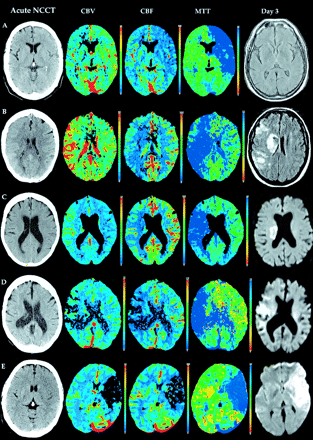

图3。病人答:孤立的局部肿胀(IFS) 41 CT (NCCT),低灌注在平均运输时间(MTT)和脑血容量增加cb v()都未对急性CT灌注(CTP)地图,也没有进展与后续梗死主要再灌注。病人B: IFS NCCT,低灌注在麻省理工,cb v和增加急性CTP地图上都未,但梗死发生没有重大进展再灌注。患者C:低灌注MTT和cb v增加急性CTP地图上都未急性NCCT没有任何变化明显。没有在皮质梗死区域主要在后续再灌注。病人D:低灌注在cb v MTT和减少急性CTP地图上都未NCCT没有任何明显变化。随后梗死出现在cb v减少区域都未随访患者E先生:深刻的cb v下降和CBF急性CTP地图,都未与相关实质hypoattenuation NCCT。在后续先生广泛梗塞。